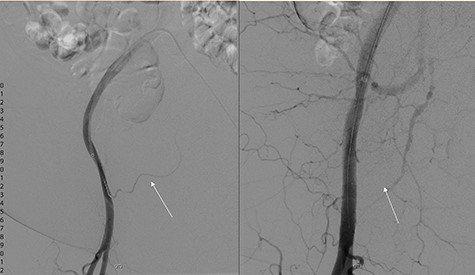

During subtracted digital angiography (DSA), the right inferior epigastric artery (IEA) could not be cannulated due to a pre-existing atherosclerotic lesion but no active contrast extravasation was noted. An 8 × 50 mm, self-expanding covered stent was deployed in the external iliac artery (EIA) across the origin of the IEA to occlude inflow and prevent recurrence of bleeding (Fig. 2). The patient recovered haemodynamically and was transferred to intensive care unit (ICU). During this procedure, a cystogram performed via the indwelling Foley catheter confirmed the correct positioning and normal outlining of the bladder with no evidence of perforation.

DSA showing left: flow through inferior epigastric artery (white arrow) and right: occlusion of inferior epigastric artery flow with covered stent in inferior epigastric artery.